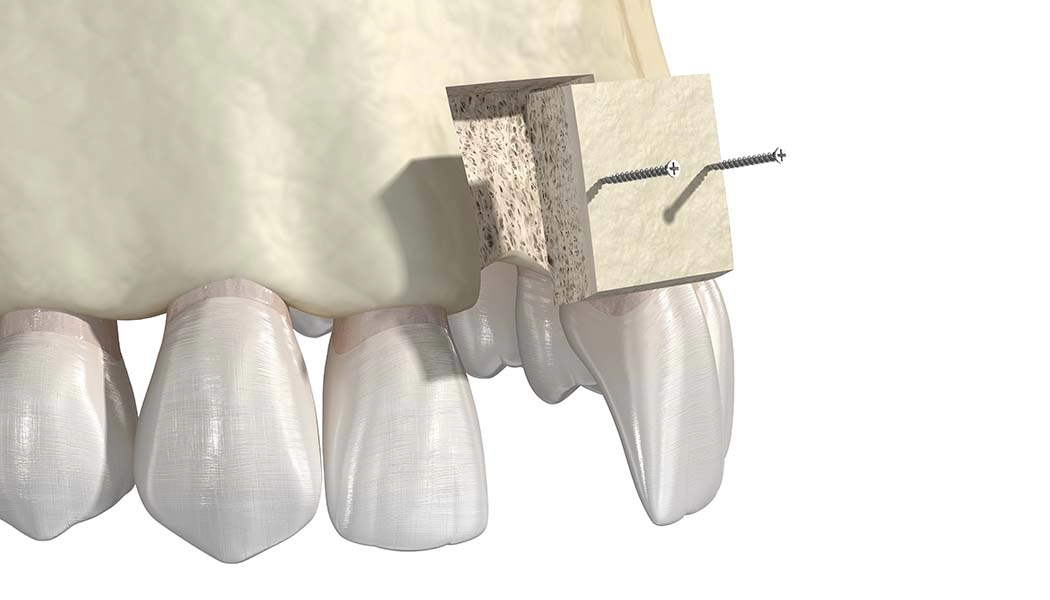

Расщепление альвеолярных отростков проводят путём механического расширения стенок гребня и заполнения образовавшейся полости костным материалом. За счет этого компенсируется нехватка ширины кости. Выполняется одномоментно с установкой имплантатов. После проведения имплантации и подсадки костной ткани десна ушивается. Метод применяется на нижней челюсти и на верхней для фронтальной зоны. При сильной вертикальной атрофии кости (нехватка высоты гребня) метод не применяется.